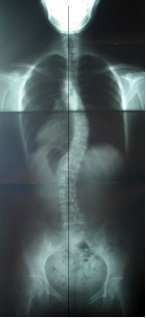

척추 측만증 치료 사례

추나요법을 위주로 하고 체형교정 바태운동을 겸하여 척추 측만증을 치료한 사례